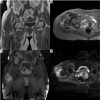

Material and methods: The conventional and diffusion magnetic resonance images (MRIs) of 42 patients operated for soft tissue sarcomas between June 2012 and March 2015 followed up with MRIs that were evaluated by 2 radiologists retrospectively. Diffusion MRIs were acquired at 4 different b-values (50, 400, 800, 1000 s/mm2). The lesions were classified according to conventional MRI findings as post-treatment changes and recurrent tumours.

Results: When the patient group with recurrent tumours was compared with the patient group with postoperative changes the ADC calculations were statistically significantly lower for the recurrent tumours at all b-levels (p < 0.001 for all b-levels). The sensitivity of b-50 values lower than 3.01 × 103 mm2/s in showing recurrent tumours was 100% and the specificity was 77.78%. The sensitivity of b-400 values lower than 2.1 × 103 mm2/s in showing recurrent tumours was 80% and the specificity was 96.3%. The sensitivity of b-800 values lower than 2.26 × 103 mm2/s in showing recurrent tumours was 100% and the specificity was 88.89%. The sensitivity of b-1000 values lower than 2 × 103 mm2/s in showing recurrent tumours was 93.3% and the specificity was 92.5%.

Conclusions: The ADC values obtained from diffusion-weighted images have high sensitivity and specificity in differentiating recurring soft tissue sarcomas during monitoring after treatment from postoperative changes.